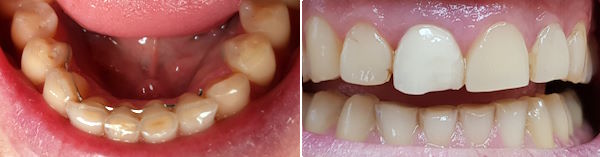

24-jähriger Patient (17.11.2025 / 8888)

Anamnese: Der Patient musste wegen einer kieferorthopädischen Behandlung 4+4 ziehen und 765+567 nach vorne verschieben lassen. Deshalb ist eine Minderbelastung des Kauzentrums 6-6 entstanden. Um besser kauen zu können, hat er nur noch links gebissen. Dabei ist aber +7 elongiert und ein Vorkontakt auf +-7 entstanden, der ihn störte. Er hat deshalb schon fünf verschiedene Knirscherschienen erhalten.

Therapie: Die mesialen Höcker des Zahnes 6- konnten ganz einfach mit Komposit erhöht werden.

Das Kaugefühl war dann sofort besser.

In der nächsten Sitzung wird auch noch der Zahn 5- erhöht, um das Kauzentrum noch etwas mehr zu vergrössern.

Vorbehalt: das Kaugefühl ist gut geblieben.

Zuerst wurde 6- erhöht, dann -6, dann 87-, dann -7 (Bild rechts unten).

Der Patient bestätigte zwei Tage später per Email, dass er mit der neuen Bisslage gut zurecht kommt.

3 Wochen später 1+1, dann +234 und dann noch 32+ (Bild rechts oben). Zuletzt fertigte ich noch eine FOS-Schiene an.

Arbeitzeit: 2+3 Stunden, Preis: 1'930 CHF